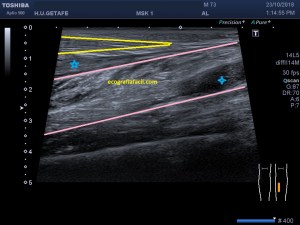

En la imagen 3 ves una imagen de un lipoma, mide 7 cms, la huella de la sonda mide 5cms, la «panoramic view» posee una regla centimetrada que sigue el contorno de la imagen, justo en la profundidad de la misma y lo marca la flecha amarilla. La profundidad la marca la flecha roja y la flecha blanca marca el rango centimetral de los 5cms, fíjate que la línea blanca es ligeramente mayor cada 5 cms. Sirve de referencia, como en la imagen 4 donde ves una colección en el glúteo de más de 10 cms.

Técnicamente es lo mismo, ambos dispositivos hacen una suma de imágenes que se plasman en un resultado final estupendo. Toda la escena más pequeña, pero más alargada que te da percepción de toda la magnitud de aquello que pretendes estudiar, te quita algo de detalle, pero te sirve para medir perfectamente y además puedes incrementar y mover la imagen con tu track ball…

Podemos medir valores superiores a los 15cms con alta calidad de imagen…podemos llegar a medir valores por encima de los 25 cms…es verdad que no todos los equipos tienen este ajuste ecográfico, es decir, es una aplicación y por tanto hay que pagarla.